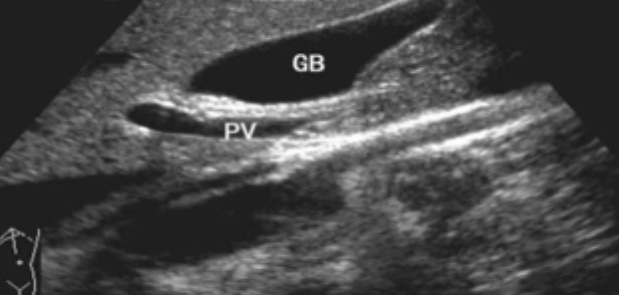

一、正常膽囊超聲圖像有的時候經常發現檢查不到膽囊,其實有幾種可能性,檢查人員的技術不過關沒發現膽囊,就要找上級醫生會診,如果還是沒找到的話就不是技術問題。結石或腫瘤充滿膽囊,使其液腔消失,慢性膽囊炎使得膽囊萎縮或膽囊壁肥厚而囊腔消失患者已進食,膽囊處於膽汁排空的狀態,膽囊先天性過小或缺失;膽囊位置極端異常(可能很低或位於左側)膽囊切除術後(注意詢問病史)。